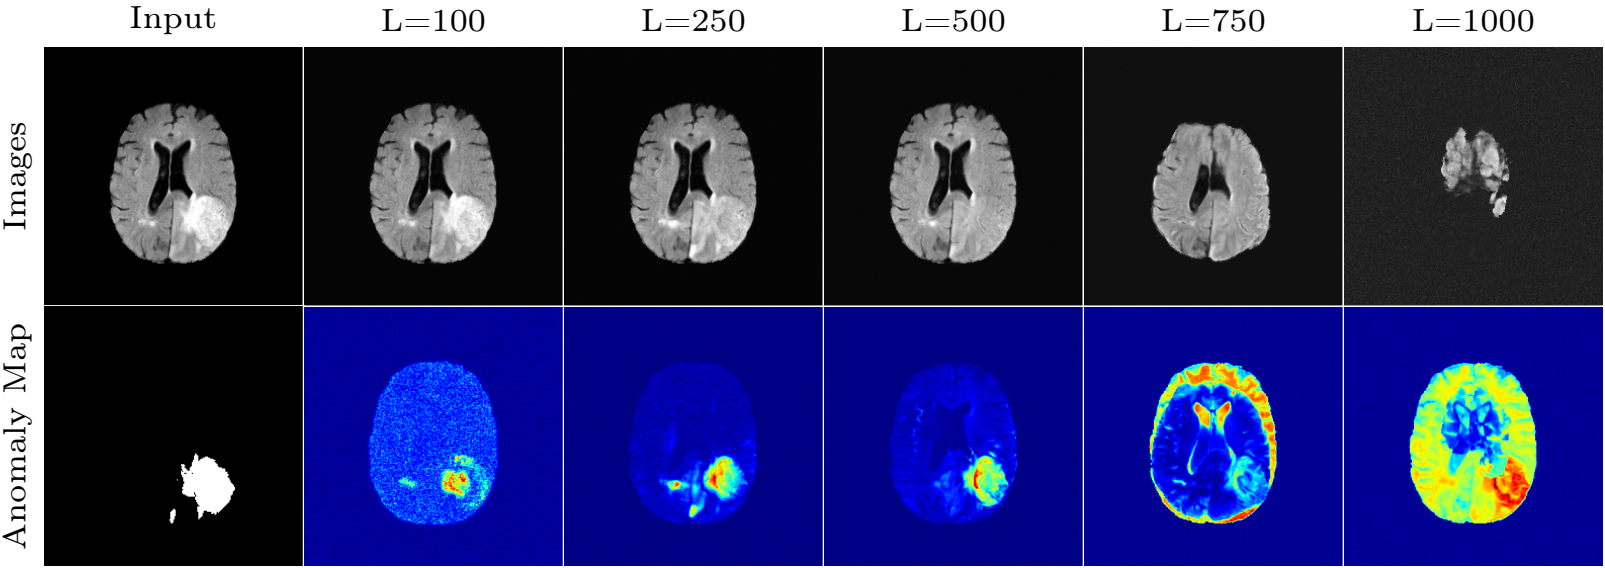

Figure 15. FLAIR image. The sampled results of various L for a fixed s = 100.

Observations:

- L too small: The model lacks enough freedom to remove the tumor;

- L too large: Images are destructed.